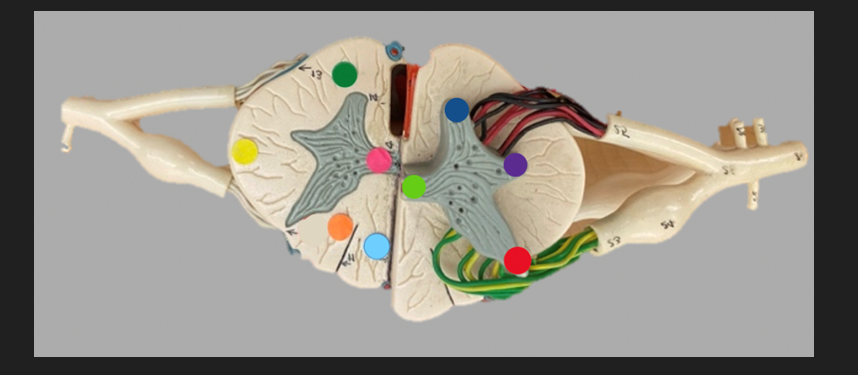

green dot

spinal nerve

orange dot

ventral root

pink dot

dorsal root

blue dot

dorsal root ganglion

red dot

dorsal ramus

yellow dot

ventral ramus

purple dot

anterior median fissure

red dot

posterior (dorsal) horn

purple dot

lateral horn

dark blue dot

anterior (ventral) horn

orange dot

dorsal column

yellow dot

lateral column

dark green

anterior column

line green and pink doit

gray commissure

light blue dot

posterior median sulcus